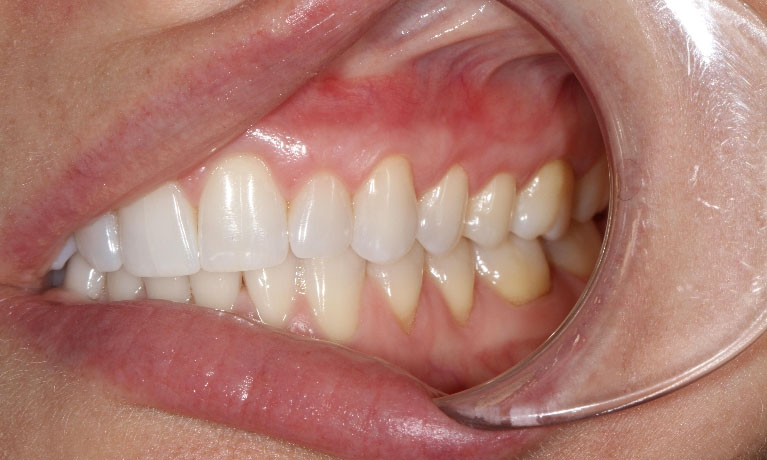

Khi răng lợi khỏe mạnh, nướu sẽ ôm chặt chân răng làm cơ sở giữ răng vững chắc và bảo vệ phần chân răng khỏi sự ăn mòn của axit. Tuy nhiên, sự bao bọc này sẽ mất đi khi nướu bị tụt. Tùy vào nguyên nhân, cơ địa và diễn biến của các yếu tố gây tụt nướu có thể chia thành 2 cấp độ tụt lợi:

Phần lợi bị teo rút nhiều khỏi bề mặt chân răng, chân răng chìa ra, thân răng dài ra thấy rõ bằng mắt thường, đi kèm các biểu hiện lợi có màu nhợt nhạt, sưng phồng, chảy máu và đau nhức lợi. Luôn có cảm giác hơi thở có mùi hôi thì nên đi khám nha khoa ngay vì tình trạng răng miệng của bạn đang ở mức báo động đấy.

Mức độ co rút của lợi được đo lường dưới 3mm thì được đánh giá là tụt lợi ở mức độ nhẹ. Đôi khi, bệnh tụt lợi nhẹ chỉ diễn ra âm thầm, không có quá nhiều biểu hiện nên chúng ta có thể không thể quan sát được. Tuy nhiên, nếu không phát hiện và khắc phục sớm thì về lâu dài cũng sẽ đưa đến hậu quả xấu do tụt lợi dần nghiêm trọng hơn.